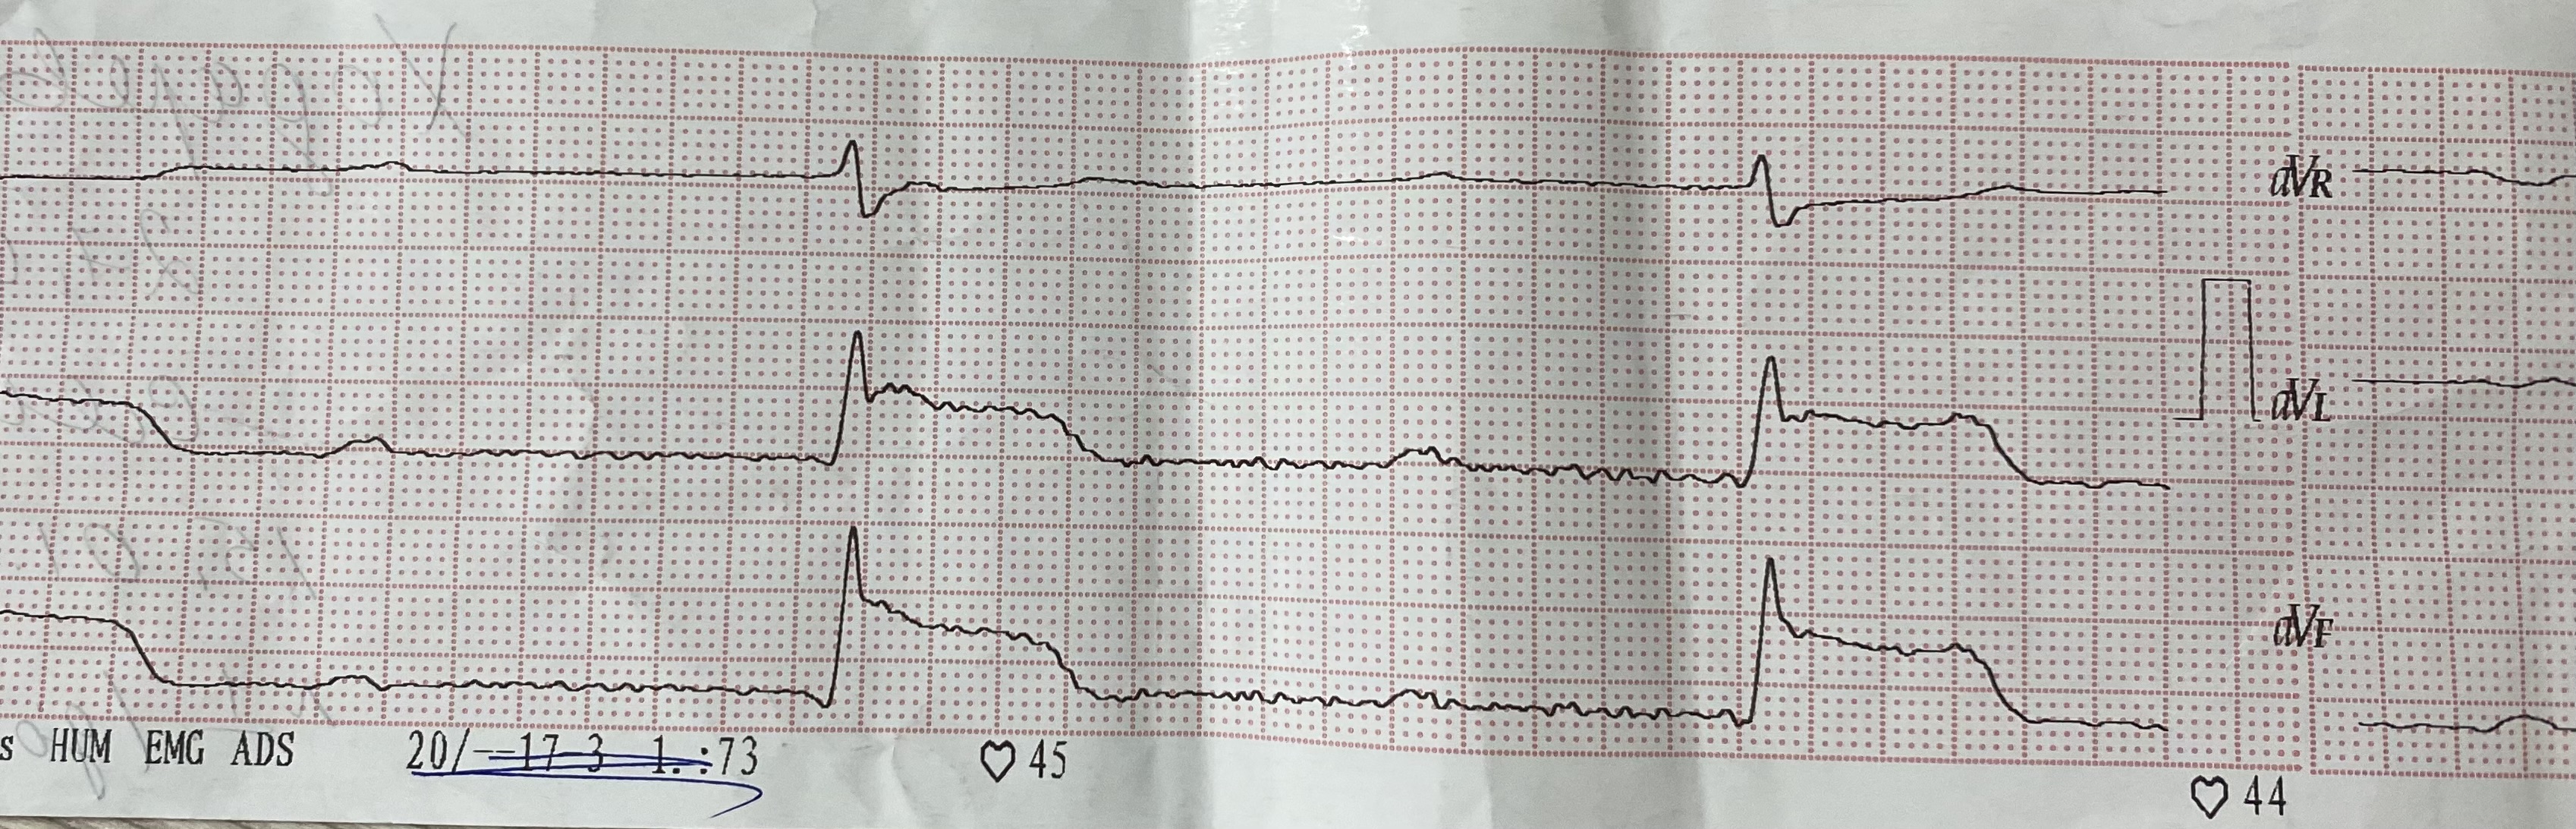

Ж 96 лет. Ав блокада 2:1. Инфаркта здесь нет.